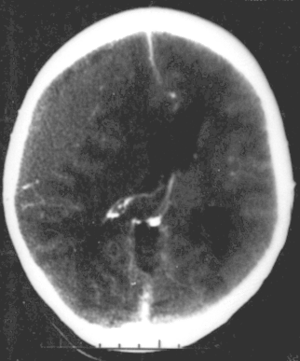

![]() | |

| Epidural hematoma, an example of a focal injury | |

- Epidural hemorrhage is bleeding between the dura mater and the skull.[4] It is commonly associated with damage to the middle meningeal artery, often resulting from a skull fracture.

- Subdural hemorrhage is bleeding between the dura mater and the arachnoid.[4]

- Intracerebral hemorrhage is bleeding within the brain tissue itself.[4]

- Intraventricular hemorrhage is bleeding within the ventricles of the brain.[4]